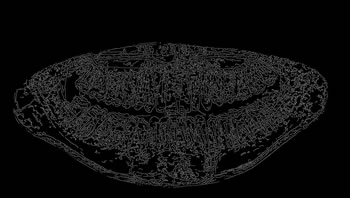

To thoroughly benchmark the methods studied here, the 1,500 images were distributed among 10 categories. The images were named, using whole numbers, in sequential order by category, aiming at not identifying the patients in the study. The process of categorizing the images was performed manually, selecting images individually, counting tooth by tooth, as well as verifying structural characteristics of the teeth. The images were classified according to the variety of structural characteristics of the teeth (see Table 5). Finally, the images were cut out to disregard non-relevant information (white border around the images and part of the spine) generated by the orthopantomograph device. After the clipping process, there was a change in the size of the images to 1991 ×\times 1127 pixels, but without affecting the objects of interest (teeth), as shown in Figure 2. The cropped images were saved on the new dimension to be used in the following stages, which will be presented in the next sections. Figure 3 shows an X-ray image corresponding to each of the categories of our data set.

Refer to caption

Figure 3: Examples of images from the data set categories of present work: (a) Category 1; (b) Category 2; (c) Category 3; (d) Category 4; (e) Category 5; (f) Category 6; (g) Category 7; (h) Category 8; (i) Category 9; (j) Category 10.